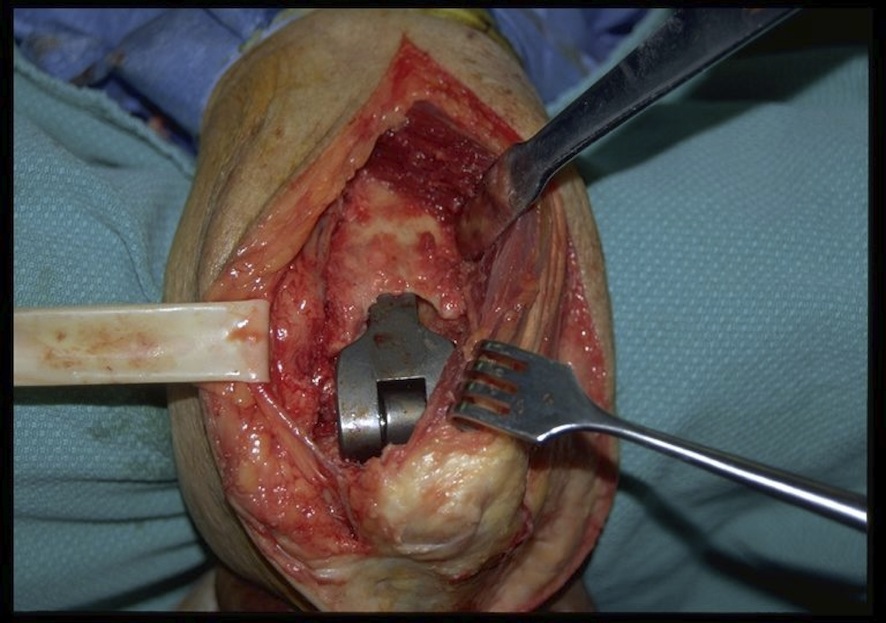

Technique

JBJS surgical technique elbow resection deep infection

Management

- systematic review of 309 TEA infections

- Staph aureus most common (42%) followed by coag neg Staph 33%

- irrigation and debridement 56%

- resection arthroplasty 71%

- one stage revision 67%

- two stage revision 81%